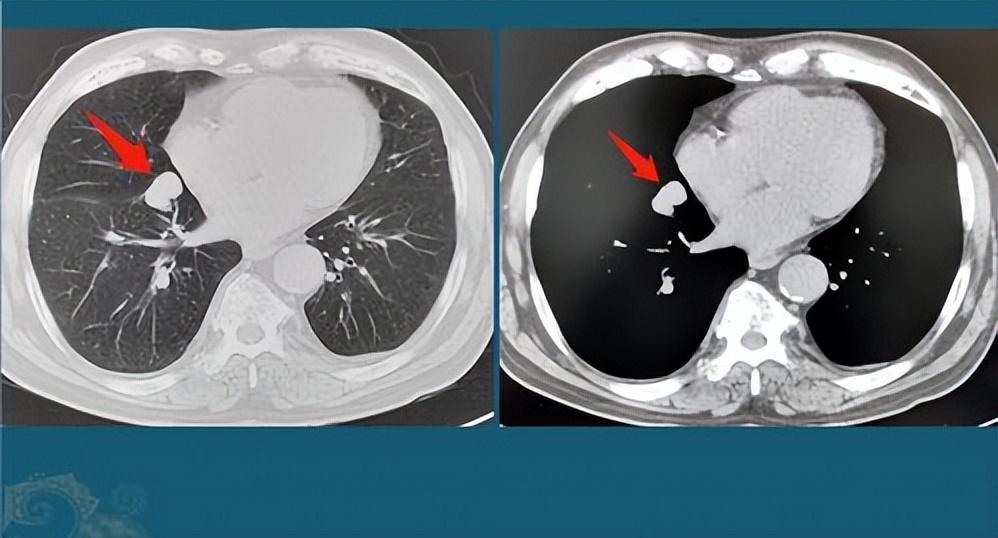

肺結(jié)節(jié)是指肺部出現(xiàn)的直徑小于3厘米的圓形或類圓形病灶,大多數(shù)肺結(jié)節(jié)是良性的,但部分可能需要治療,肺結(jié)節(jié)的癥狀因個(gè)體差異而異,部分患者在早期可能無(wú)任何癥狀,因此定期進(jìn)行體檢至關(guān)重要。